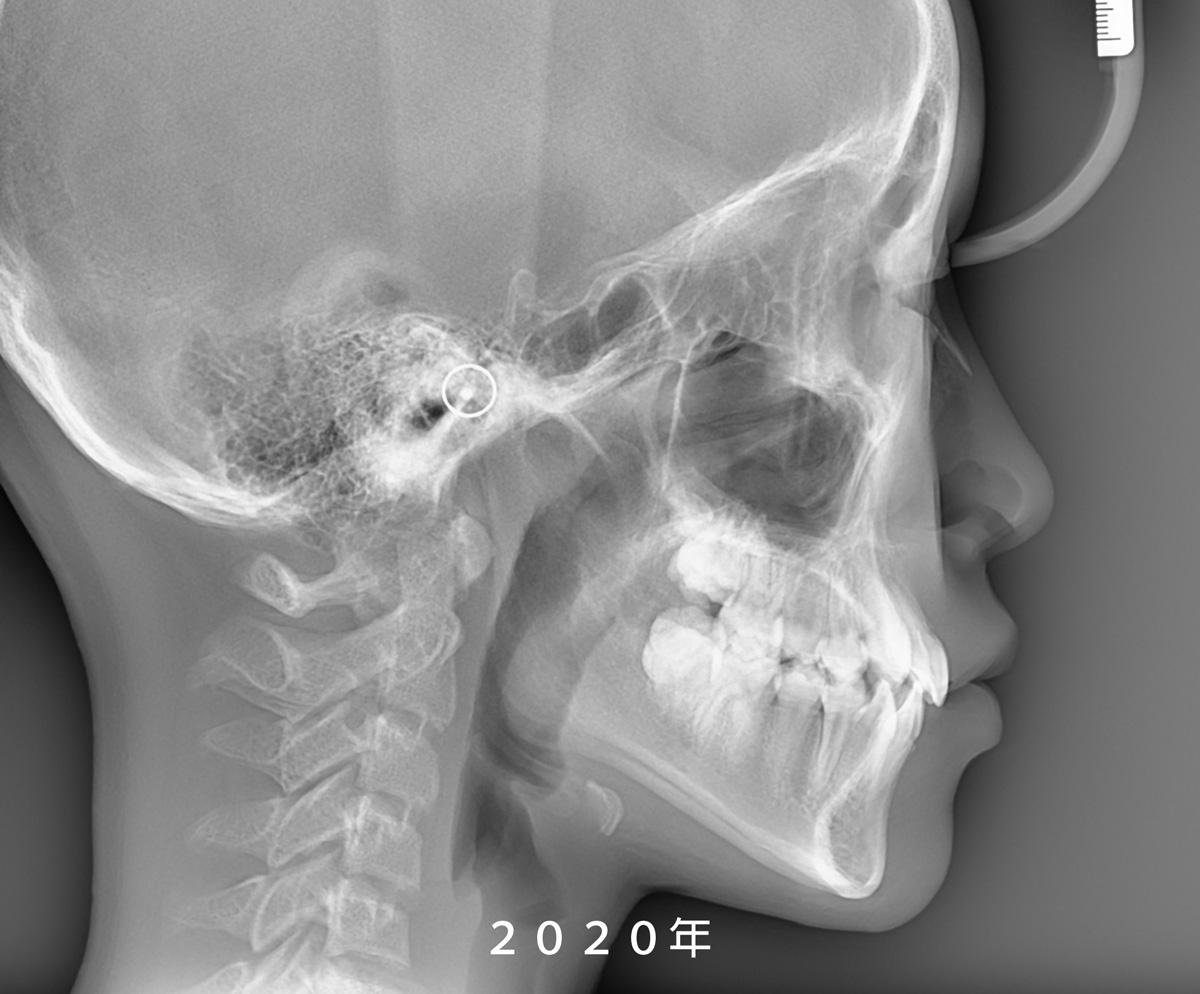

柯醫師仔細檢查後發現,小妘的牙齒擁擠是因為「牙弓過窄」,造成空間不足,才會讓牙齒錯位。此外,透過Steiner測顱分析發現,小妘的ANB夾角只有0.82度,屬於骨性三級關係,也就是常說的「骨性戽斗」。

雖然,小妘從12歲開始接受矯正治療,當時牙齒和下巴都還有不少成長潛力,治療過程中必須謹慎觀察發育變化,以期在治療結束後達到最穩定、自然的咬合與笑容。

After examining Yun, Dr. Ko found that her crowding was caused by a narrow dental arch, leaving too little space for proper alignment. Steiner analysis also showed an ANB angle of 0.82 degrees—evidence of a skeletal Class III underbite.

Starting treatment at age 12 meant her teeth and lower jaw still had significant growth potential, so careful monitoring was key. This allowed Dr. Ko to guide her toward a stable, natural bite and a smile that would grow with her.

從 X 光片重疊影像可以發現,

她的鼻子與下巴都有明顯的成長變化,

但所幸前牙並未發展成

我們較為擔心的反咬(negative overjet)問題。